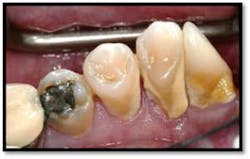

UL/LL reflected in a mirror and UL/LL radiograph

Treatment: FM Perioscopy completed in two, 2-hour sessions with local anesthetic and micro ultrasonics. No hand instruments are necessary during Perioscopy.

Note: When instrumenting “blindly,” the end point is unknown and debris is left behind. Visualization via the Perioscopy System ensures effective treatment is rendered because the bioburden is completely removed. Ultrasonic instrumentation is not only effective and efficient for thorough bacterial removal, but is an easier therapy to tolerate for the patient, with less sensitivity post treatment.9 months Post Treatment: